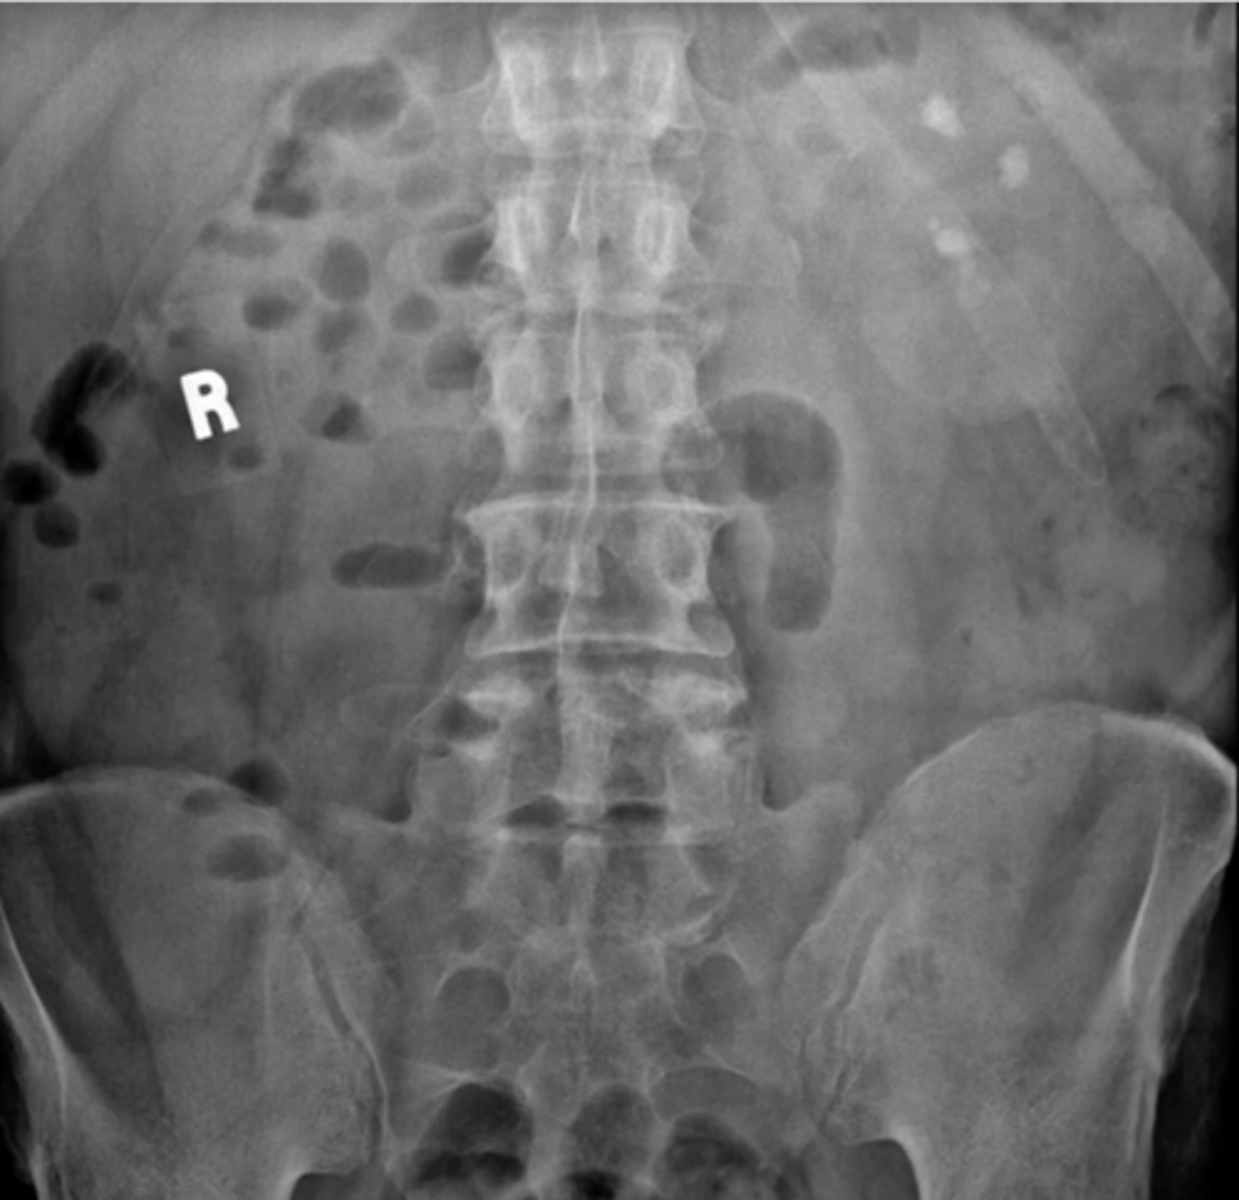

Normal bowel gas pattern

Normal supine AXR